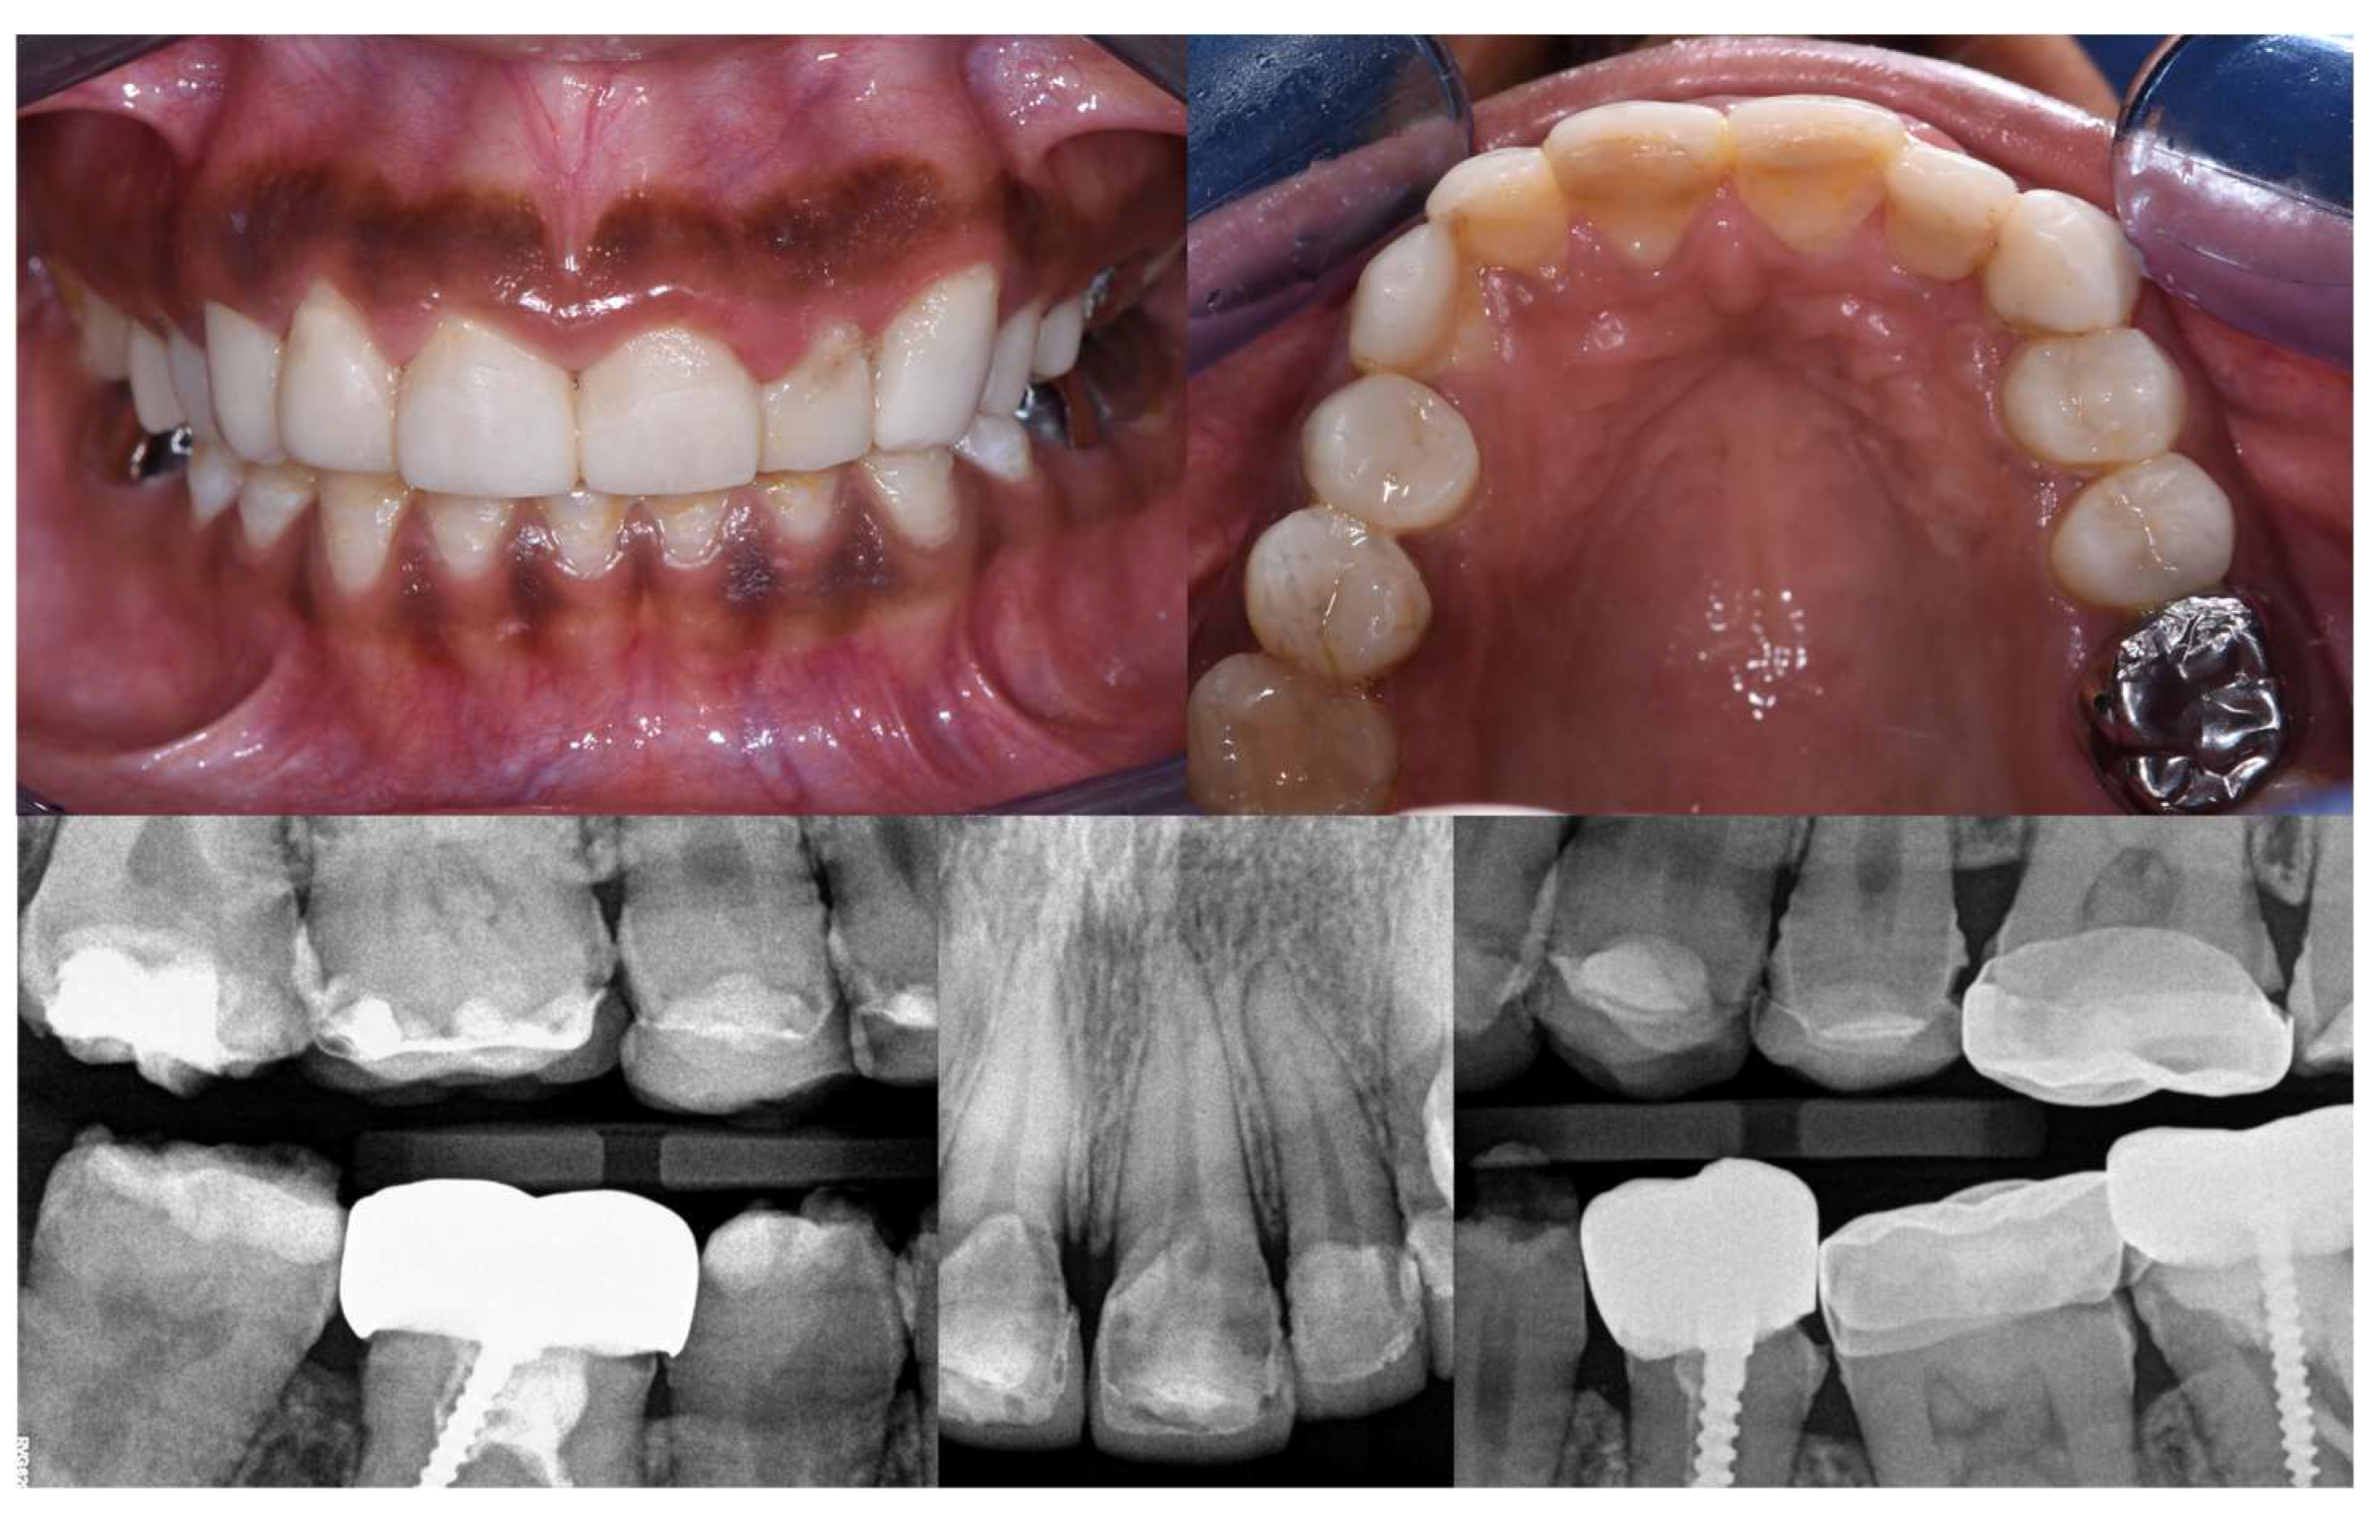

2.11.4. At One and a Half Years

2.11.5. At Three Years